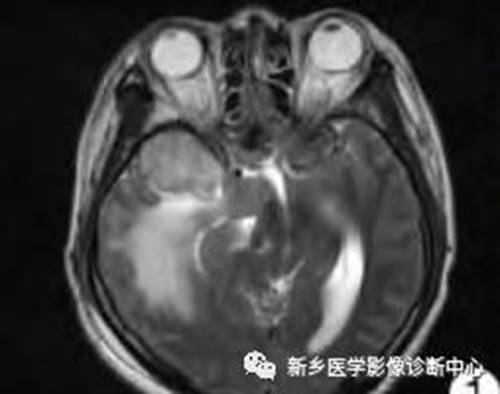

病例1:

病例2:

TIWI C 显示病灶增强,呈囊、实性。MRS 病灶内波谱显示Cho峰明显升高,Cr、NAA峰无或甚低,出现GHS、Gly峰。虽肿瘤呈分叶状,但囊性区(体素4)不见Lip峰,提示为囊变而非坏死,且无明显瘤周浸润,故应诊断为良性囊性脑膜瘤。

病例3:

TIWI C 显示病灶呈实质性增强,FLAIR呈高信号,边缘见血管伸入。MRS 病灶内波谱显示Cho峰明显升高,无NAA峰, 出现GHS、Gly峰,并见到Lip峰。结合常规MRI所见,以及 Lip峰不高和瘤周(体素4)浸润不明显,提示含脂肪化生细胞较多的良性脑膜瘤可能为大,但恶性脑膜瘤不能除外。病理图片显示泡沫细胞,可能为出现Lip峰的原因。